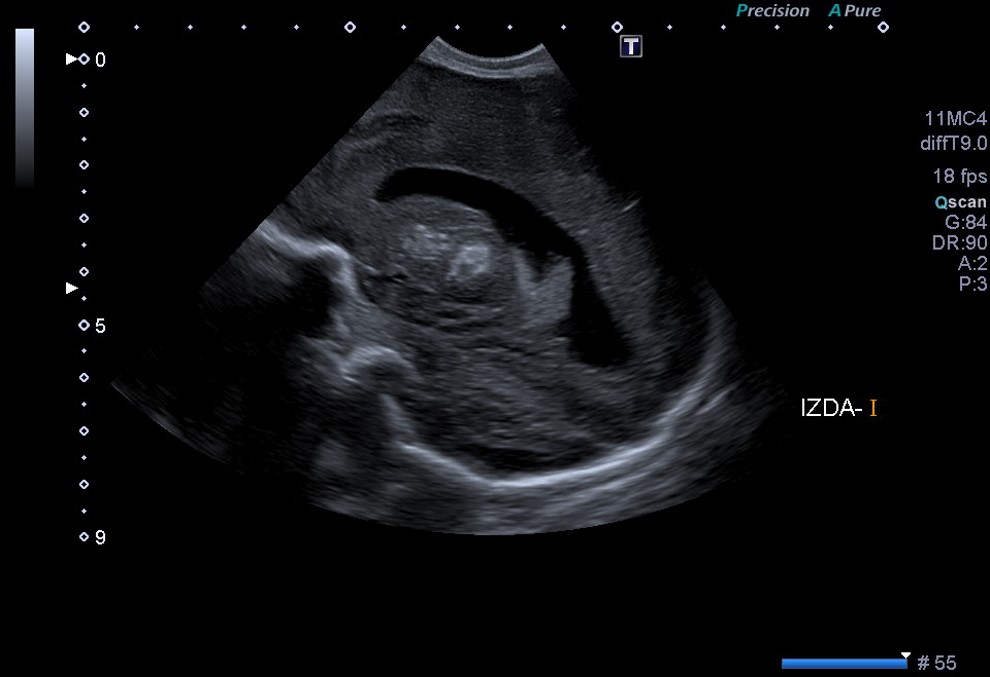

En el corte coronal y parasagital de la ecografía cerebral (Fig. 1A y 1B) se aprecian calcificaciones parenquimatosas, en ganglios de la base y en el tálamo. También se aprecia un quiste de septum prominente para la edad gestacional a término.

Figura 1B. USc. Corte parasagital izquierdo (S2)